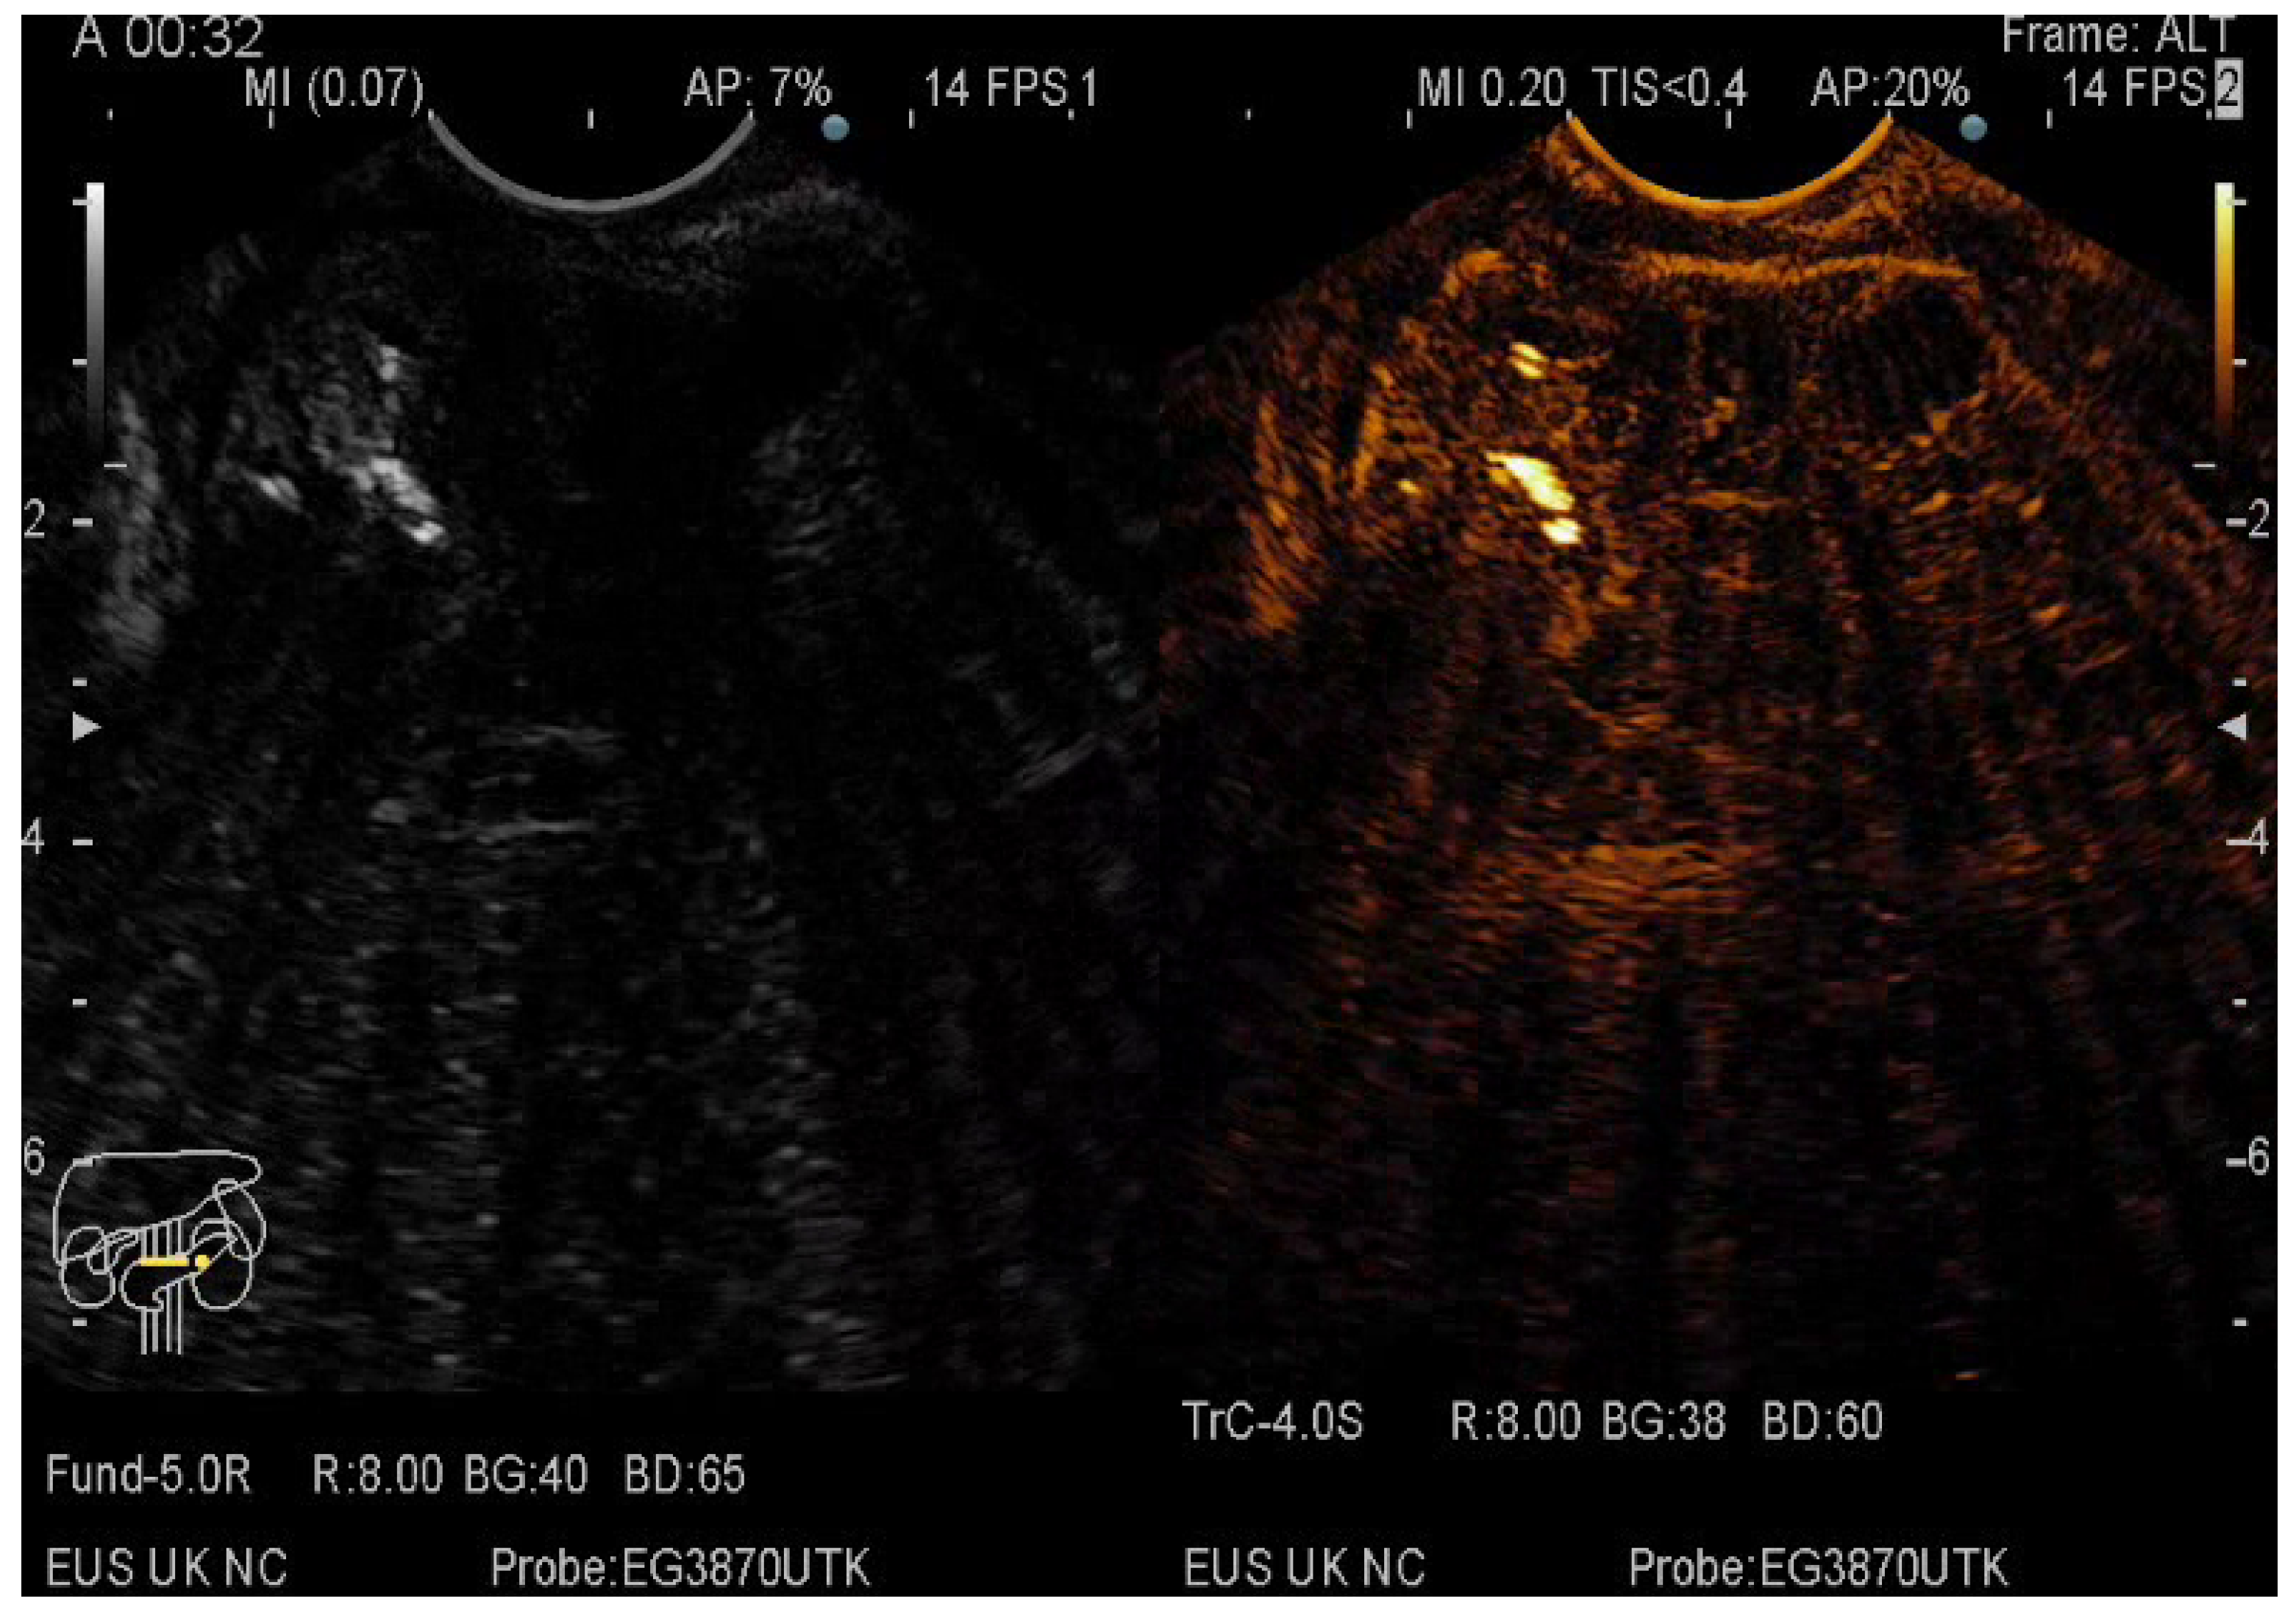

The pancreatic masses where located as it follows: 2/3 at the head level and 1/3 at the level of the body and tail. The size of the pancreatic masses ranged from 10 to 78 mm, with an average diameter of 35 mm. For obtaining the core tissue, fanning technique was applied with a mean number of needle passes of 2 and a range from 2 to 5 passes. Final pathology revealed pancreatic ductal adenocarcinoma–PDAC (149) (Figure 3), mass-forming pancreatitis–MFP (57) (Figure 4), pancreatic neuroendocrine tumors–pNETs (23) (Figure 5 and Figure 6), undifferentiated carcinoma (17), mucinous carcinoma (5), and pancreatic metastasis (5).

Figure 4.

CE-EUS image of a MFP revealing a solid mass with hyperenhancement in the arterial phase and no wash-out in the venous phase.

In 48% of the cases, the pancreatic lesion was described as hypoenhancing, with a final diagnosis of malignancy. Regarding the enhancement patterns, hypovascularity in both arterial and venous phase was associated with PDAC, hypervascularity or isovascularity in both phases were associated with either MFP or NETs, whereas the carcinomas were hypervascular (Table 6). A heterogeneous appearance with non-enhancing areas was noted in a small percentage of the hypoenhancing lesions and it might suggest necrosis. The overall diagnostic accuracy was 91%.